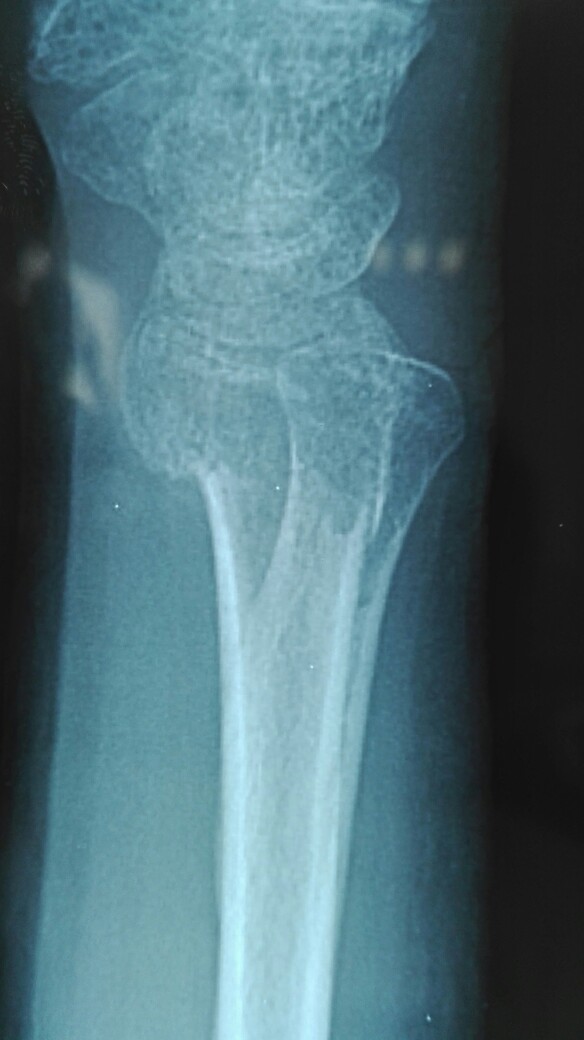

患者小夹板固定术后42天,复查,移除外固定,进行功能锻炼!